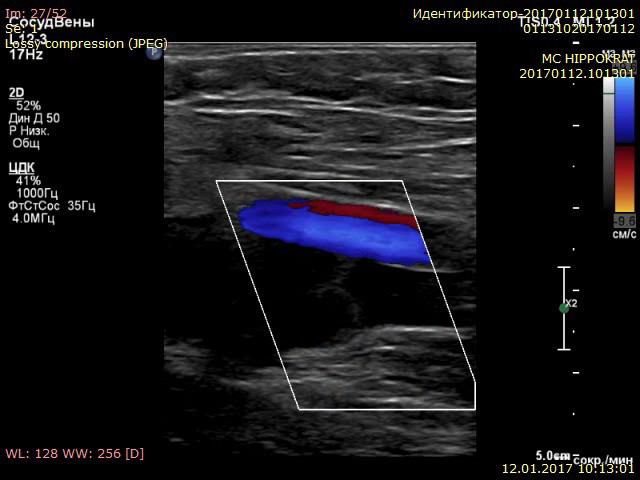

Видео узи артерий

Видео узи артерий 107 фото